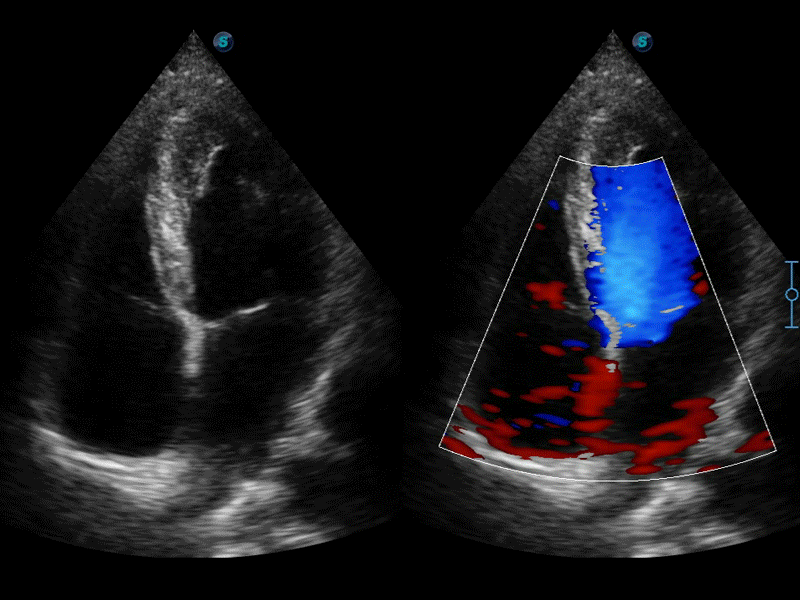

高分辨率血流成像技術提高了對低速血流信號的檢測能力。在提高空間分辨率的同時,也克服了血流外溢現象,為用戶提供更加真實的血流動力學信息。